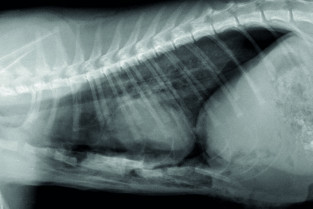

Le GEIM vous propose une séance de travaux pratiques de radiographies sur le thorax. Tous les aspects sont abordés sous la forme de TP de lecture de radiographies numériques sur station de travail Osirix sur Mac (3 vétérinaires maximum/ordinateur).

- adopter une méthodologie pour interpréter les affections de la cage thoracique, de la plèvre, et du médiastin chez les carnivores domestiques ;

- connaître l’aspect normal et anormal de la cage thoracique, de la plèvre, et du médiastin chez les carnivores domestiques.